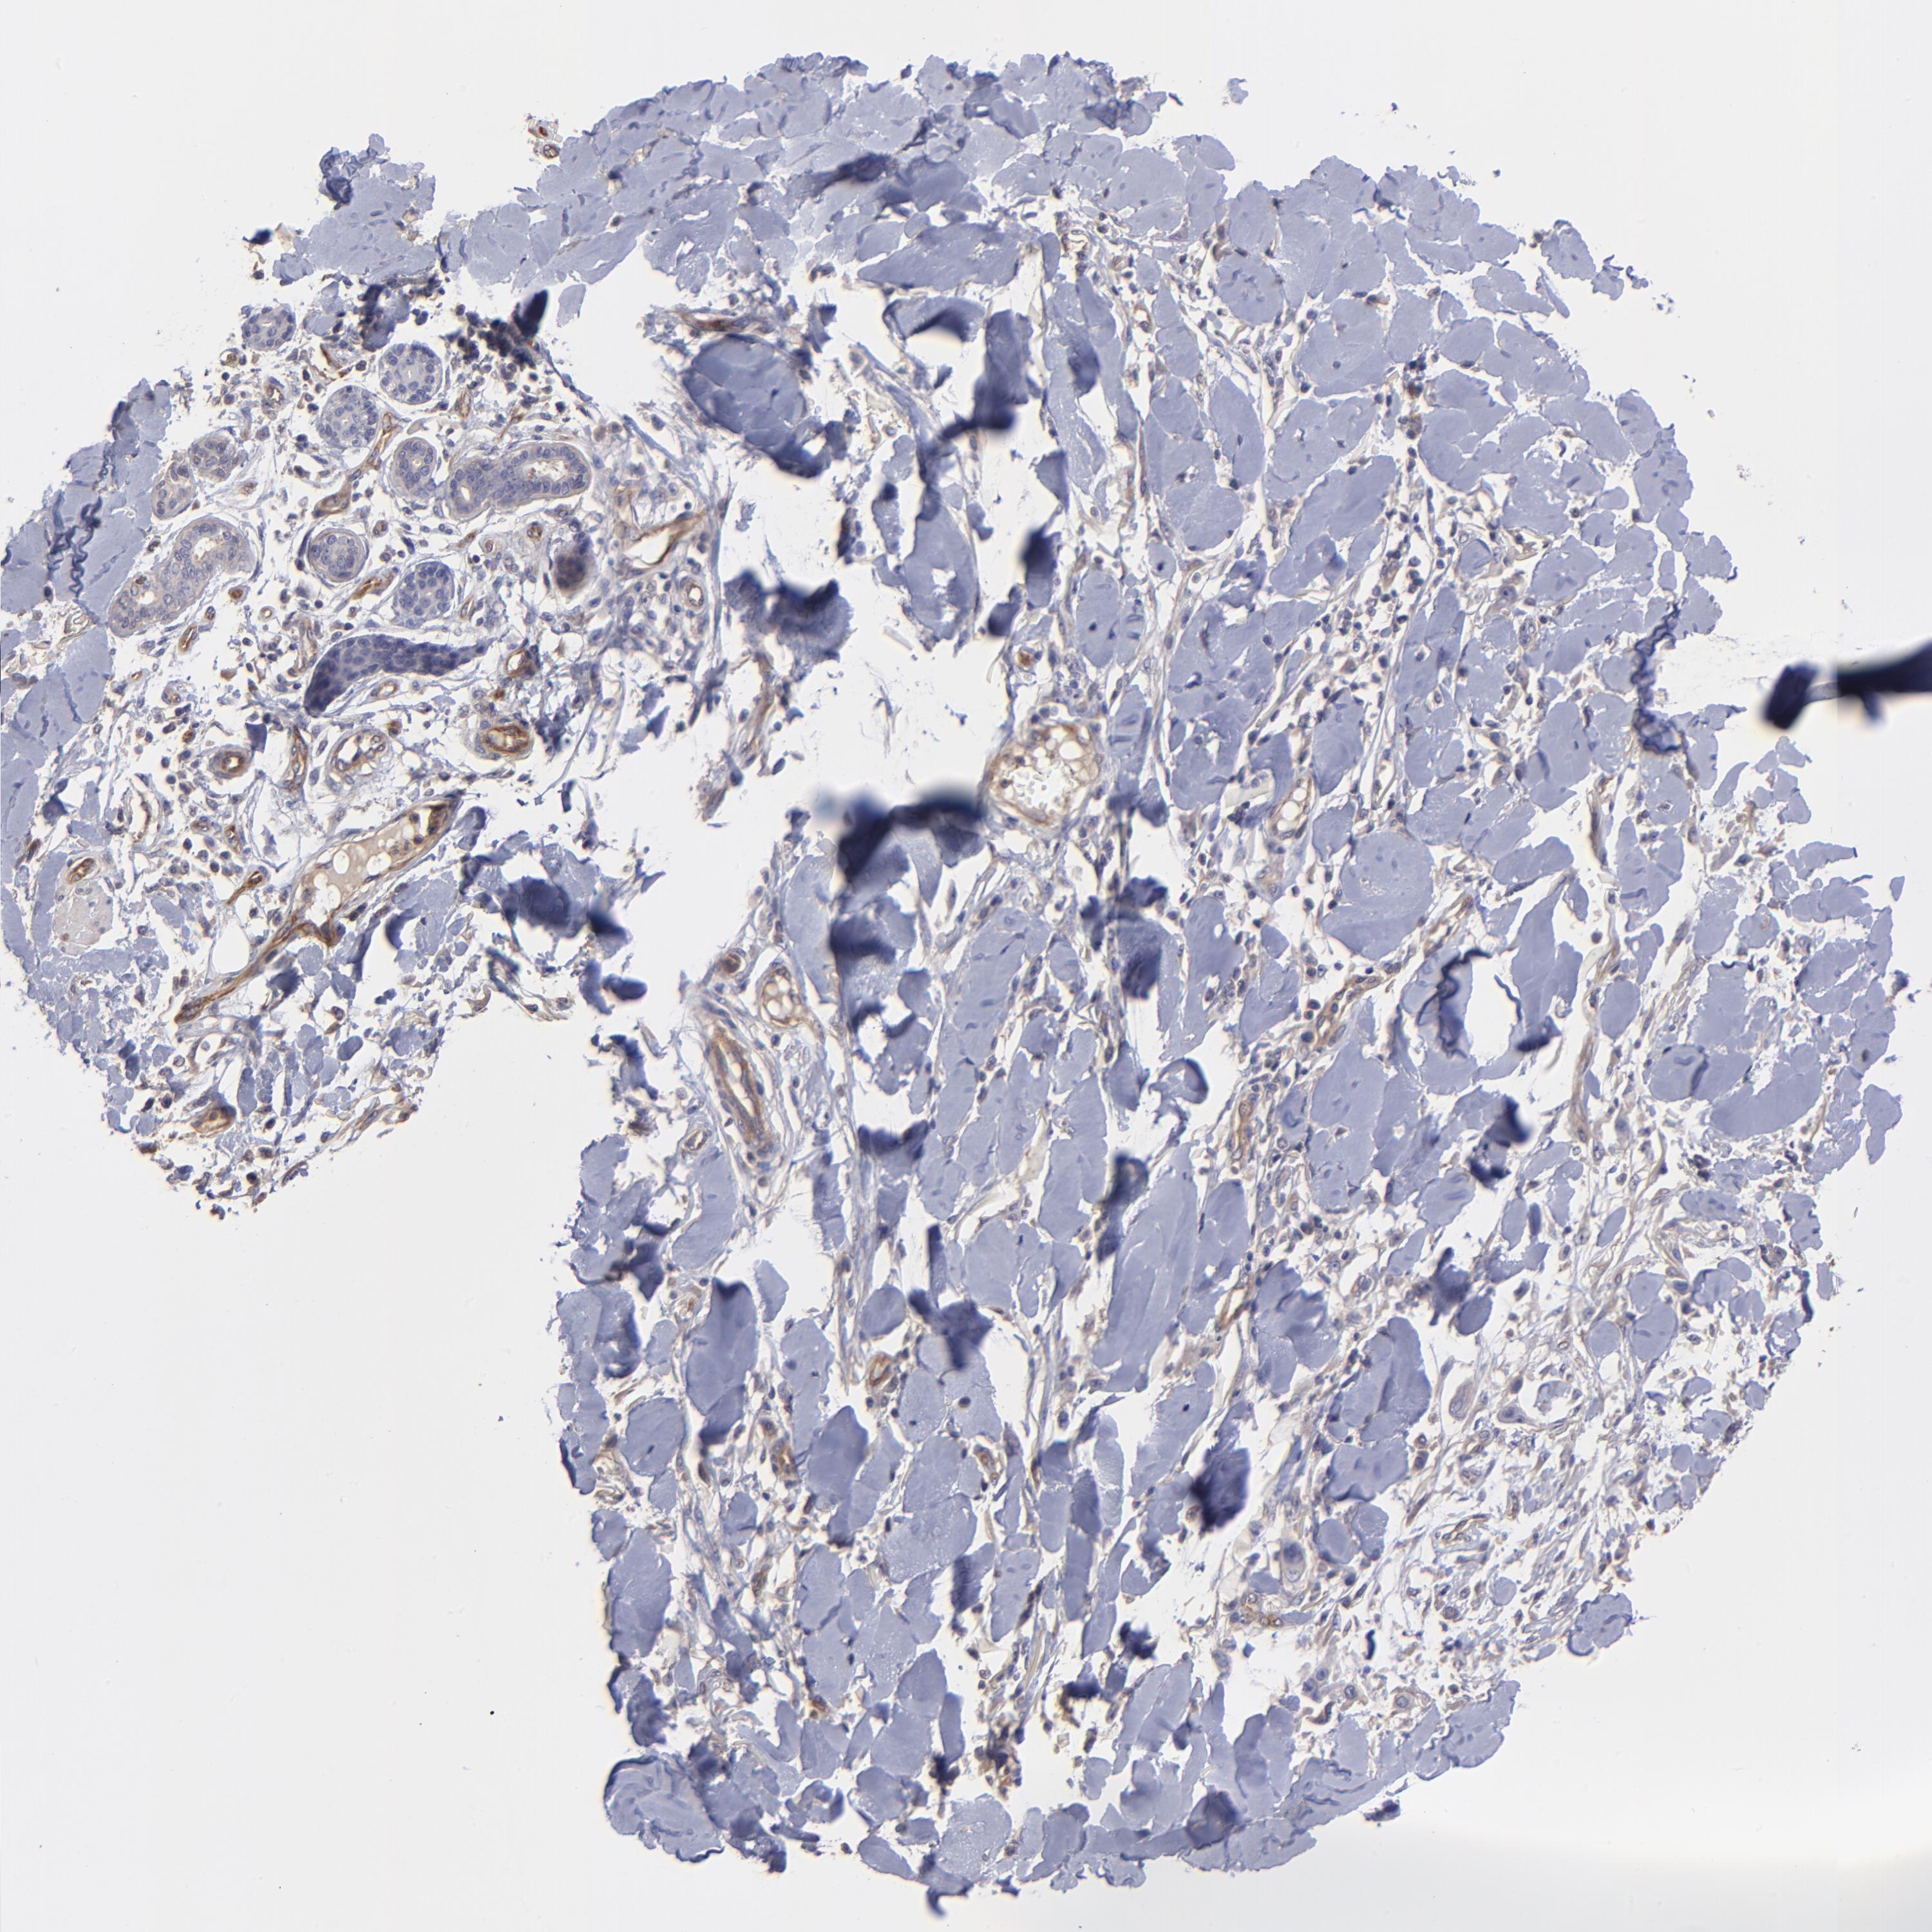

SKIN CANCER - Protein expressioni

A mouse-over function shows sample information and annotation data. Click on an image to view it in a full screen mode. Samples can be filtered based on level of antibody staining by selecting one or several of the following categories: high, medium, low and not detected. The assay and annotation is described here.

Antibody stainingi

Antibody staining in the annotated cell types in the current human tissue is reported as not detected, low, medium, or high, based on conventional immunohistochemistry profiling in selected tissues. This score is based on the combination of the staining intensity and fraction of stained cells.

Each image is clickable and will lead to virtual microscopy that enables deeper exploration of all samples and also displays staining intensity scores, fraction scores and subcellular localization as well as patient and tissue information for each sample.

Antibody HPA003300

Squamous cell carcinoma, NOS

Basal cell carcinoma